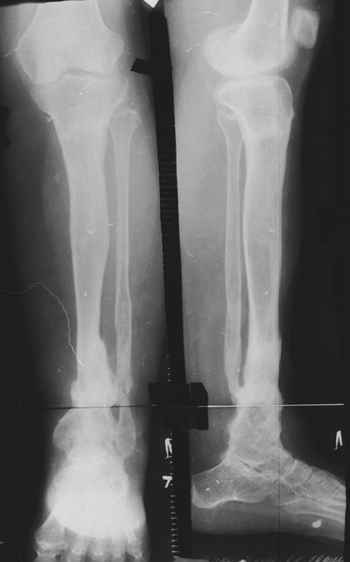

Врождённый Псевдоартроз Голени (ВПГ) – редкое заболевание б частота 1: 190000 живых новорожденных.

До 1930 года ампутация была регулярной процедурой. Но в последние 80 лет произошла смена представления к лечению ВПГ. Около 70% пациентов псевдоартроз большеберцовой кости (б/б) сопровождается таковым малоберцовой (м/б).

Женщина 28 лет, пошедшая 13 предыдущих оперативных вмешательств по-поводу ВПБ имела 9 см. укорочения.